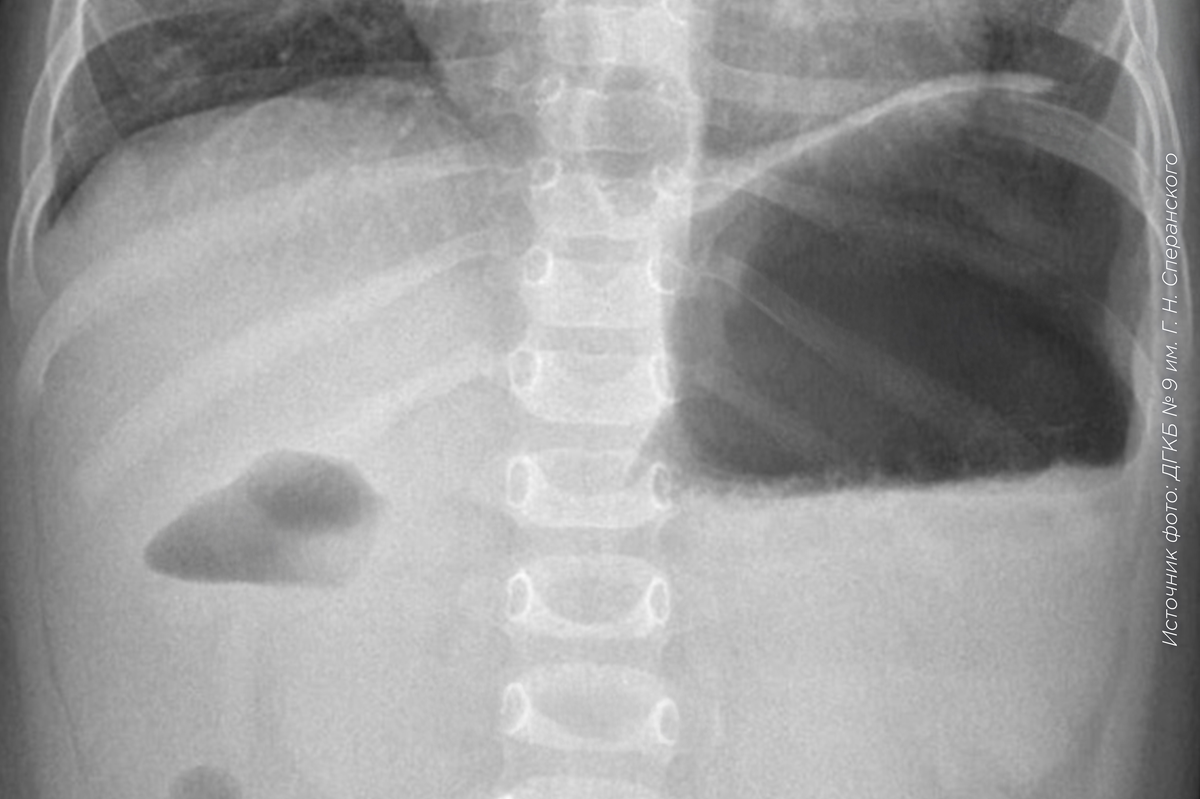

В ДГКБ № 9 им. Г. Н. Сперанского поступила семимесячная девочка с ежедневными приступами рвоты. Обследование выявило редкую патологию: в двенадцатиперстной кишке ребенка сформировалась толстая мембрана.

Несмотря на патологию, до семи месяцев ребенок получал все питательные вещества через узкое отверстие, но к моменту поступления мембрана практически полностью блокировала прохождение пищи. Девочке требовалась операция.

Через аккуратный разрез хирурги больницы ликвидировали препятствие. Операция прошла успешно, сейчас девочка полноценно усваивает пищу и получает необходимые вещества.